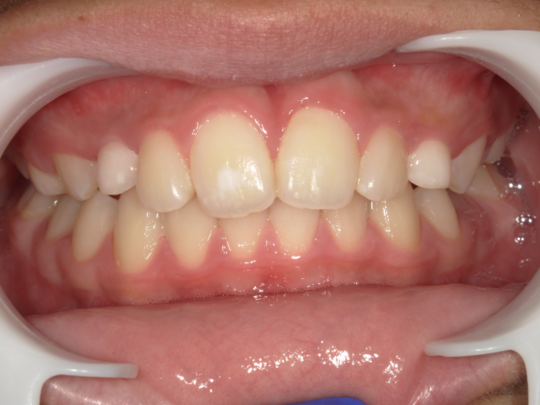

治療後

治療前

治療説明 歯科矯正で取り外し可能な矯正方法である床矯正で治療しました

治療期間 4年

治療費用200000 円

治療の副作用(リスク)歯の動き方には個人差があり、予想された治療期間が延長する可能性があります。。床矯正の使用状況、矯正歯科治療には患者さんの協力が必要であり、それらが治療結果や治療期間に影響します。2次矯正が必要になる場合もあります。